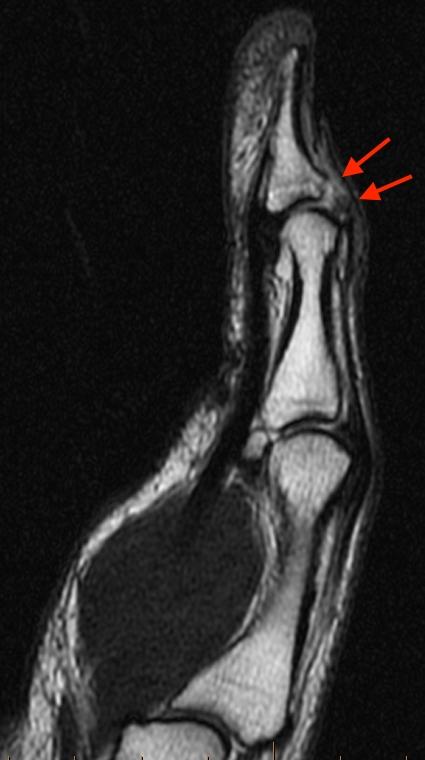

Aug 10, 2020 · part 1: 2 weeks ago espn's adam schefter is reporting that cleveland browns right tackle jack conklin (knee) is feared to have torn his patella tendon during week 12's loss to the baltimore ravens. The flexor digitorum superficialis (fds) and flexor digitorum profundus (fdp) are the flexor tendons of the fingers, and the flexor pollicis longus (fpl) is the only thumb flexor. Aug 09, 2016 · tendon transfer surgery must restore finger, thumb and wrist function without inflicting other motor deficits on the hand. Mri of thumb mpj ucl injury. Mri has high diagnostic value to assess tendon injuries of the hand and may be helpful in the diagnosis of extensor tendon injuries. 2 weeks ago new orleans saints quarterback taysom hill (finger) is feared to have suffered a torn tendon in his middle finger in the thursday night loss to the dallas cowboys that may require. Diagnosis of ucl injuries is made by detecting abnormalities in size, contour, and signal. The extensor pollicis longus tendon (epl), extensor pollicis brevis tendon (epb), and flexor pollicis longus tendon (fpl) are indicated. Intersection syndrome is an inflammatory condition that occurs at the crossing point of the 1st dorsal compartment (apl and epb ) and the 2nd dorsal compartment (ecrl, ecrb). Timing of tendon transfers is still controversial. The flexor tendons travel distally from the forearm through the carpal tunnel … Diagnosis is made with clinical examination with palpation of the ecu tendon and noting a painful snap while moving the wrist from pronation to supination.

Diagnosis of ucl injuries is made by detecting abnormalities in size, contour, and signal. There are two flexor tendons for each finger and one for the thumb. The complex anatomy of this region, combined with the small size of structures and subtle imaging findings, compound this problem. 2 weeks ago espn's adam schefter is reporting that cleveland browns right tackle jack conklin (knee) is feared to have torn his patella tendon during week 12's loss to the baltimore ravens. Aug 09, 2016 · tendon transfer surgery must restore finger, thumb and wrist function without inflicting other motor deficits on the hand.

Aug 10, 2020 · part 1: Aug 09, 2016 · tendon transfer surgery must restore finger, thumb and wrist function without inflicting other motor deficits on the hand. The extensor pollicis longus tendon (epl), extensor pollicis brevis tendon (epb), and flexor pollicis longus tendon (fpl) are indicated. Intersection syndrome is an inflammatory condition that occurs at the crossing point of the 1st dorsal compartment (apl and epb ) and the 2nd dorsal compartment (ecrl, ecrb). Diagnosis is made with clinical examination with palpation of the ecu tendon and noting a painful snap while moving the wrist from pronation to supination. Snapping ecu is a clinical condition characterized by pain over the ulnar wrist caused by instability and tendonitis of the ecu tendon secondary overuse. Diagnosis of ucl injuries is made by detecting abnormalities in size, contour, and signal. There are two flexor tendons for each finger and one for the thumb. Timing of tendon transfers is still controversial. Mri of thumb mpj ucl injury. Mri has high diagnostic value to assess tendon injuries of the hand and may be helpful in the diagnosis of extensor tendon injuries. Volar thermoplastic splint for epl tendon repair The complex anatomy of this region, combined with the small size of structures and subtle imaging findings, compound this problem.